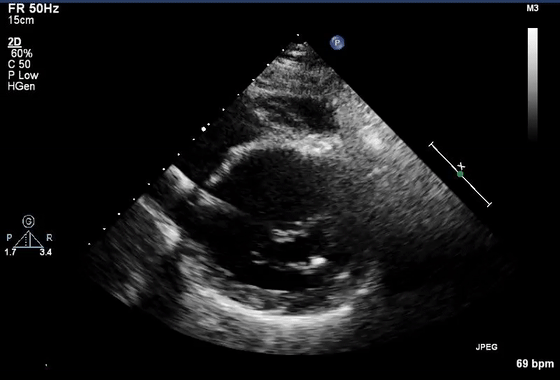

7、近场杂波

由于探头换能器本身的高振幅振荡,近场结构有时会被遮蔽,造成所谓的近场杂波。这在怀疑有心尖室血栓的病例中尤其重要(图7,视频10)。谐波成像的引入和换能器设计技术的进步已经减少了这种伪影的发生。

图7 心尖四腔视图中的近场杂波(箭头),疑似心尖血栓。(视频10)显示正常的心尖心肌动力学,杂乱回波和心肌运动之间没有关系。